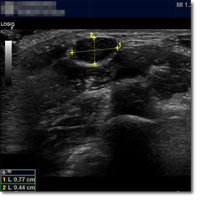

Niño de 7 años que acude a consulta de Atención Primaria por aparición de tumoración cervical de...

Álvarez García J, Sáez López E, Mateos Torre P.

23 septiembre 2025